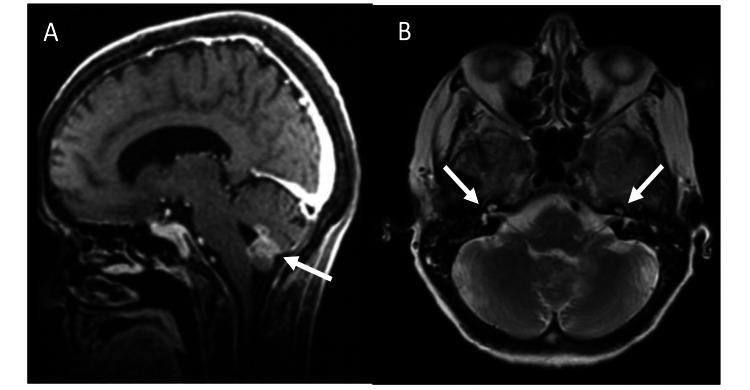

Bilateral vocal cord paralysis (BVCP) most commonly occurs secondary to iatrogenic injury and/or malignancy, but can also be a consequence of central nervous system (CNS) pathology. We report a case of BVCP secondary to leptomeningeal consequence in the context of unknown primary malignancy. The aim of this report is to promote awareness for BVCP caused by rare CNS pathology and highlight the importance of complete neoplastic and paraneoplastic workups in new-onset BVCP with unclear etiology. Here, we present a case report and review of the literature. A 68-year-old female presented with new-onset BVCP in the context of progressive dysphagia in addition to rectal and urinary incontinence. She underwent an awake tracheostomy. Her infectious and paraneoplastic workups did not identify a cause for her BVCP. Her brain MRI demonstrated enhancement of multiple cranial nerves, spine MRI demonstrated leptomeningeal enhancement, and cerebrospinal fluid (CSF) cytology was positive for metastatic adenocarcinoma. Her functional status was poor and she was deemed ineligible for chemotherapy and transitioned to palliative care. She died three months following her hospital admission. Leptomeningeal metastasis is a rare cause of new-onset BVCP. Airway management remains a critical component in BVCP. The sudden onset of BVCP in the context of generalized neurologic symptoms or cranial nerve deficits should prompt complete neoplastic and paraneoplastic investigation.

双侧声带麻痹(BVCP)最常见于医源性损伤和/或恶性肿瘤继发,但也可能是中枢神经系统(CNS)病变的结果。我们报告一例在原发性恶性肿瘤不明的情况下,继发于软脑膜病变的BVCP病例。本报告的目的是提高对罕见中枢神经系统病变所致BVCP的认识,并强调在病因不明的新发BVCP中进行全面肿瘤及副肿瘤检查的重要性。在此,我们呈现一例病例报告并对文献进行综述。一名68岁女性,除了直肠和尿失禁外,还因进行性吞咽困难出现新发BVCP。她接受了清醒气管切开术。她的感染性及副肿瘤检查未发现其BVCP的病因。她的脑部磁共振成像(MRI)显示多条颅神经强化,脊柱MRI显示软脑膜强化,脑脊液(CSF)细胞学检查转移性腺癌呈阳性。她的功能状态较差,被认为不适合化疗,转而接受姑息治疗。她入院三个月后死亡。软脑膜转移是新发BVCP的罕见病因。气道管理仍是BVCP的关键组成部分。在出现全身性神经症状或颅神经缺损的情况下,BVCP的突然发作应促使进行全面的肿瘤及副肿瘤检查。